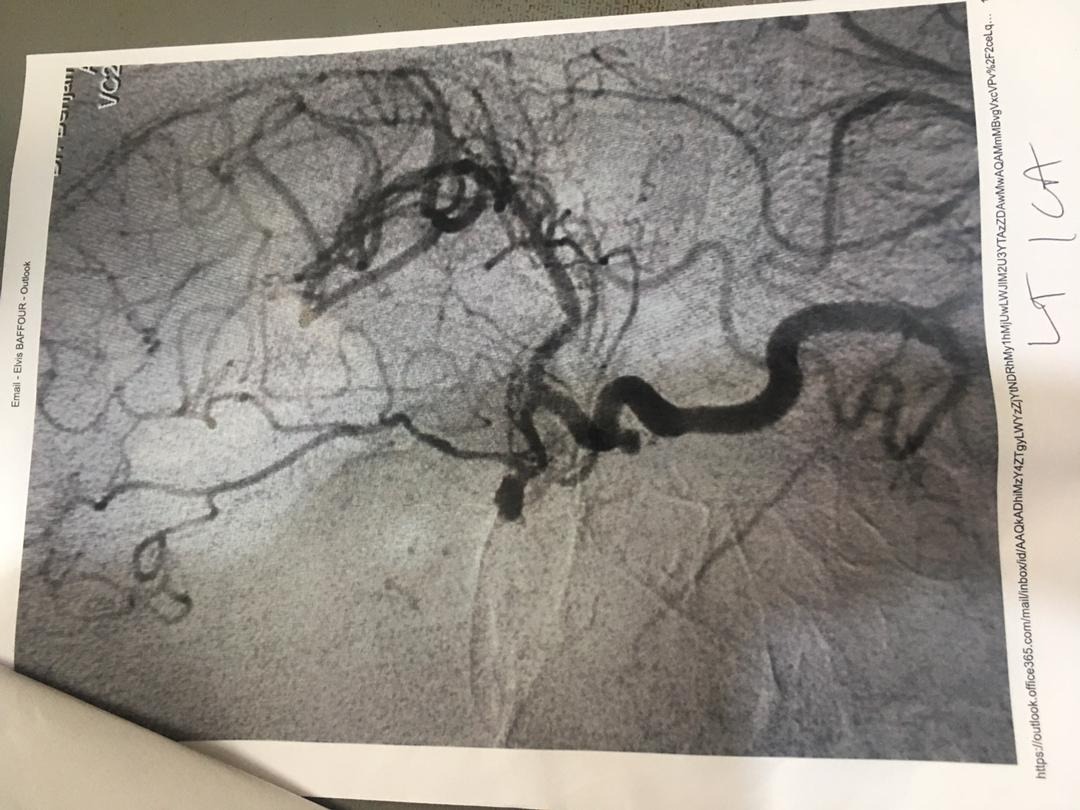

Attached is a copy of her medical scan report (2023) from Euracare Advanced Diagnostics and Heart Centre, Accra, confirming her diagnosis and the recommendation for urgent endovascular coiling.